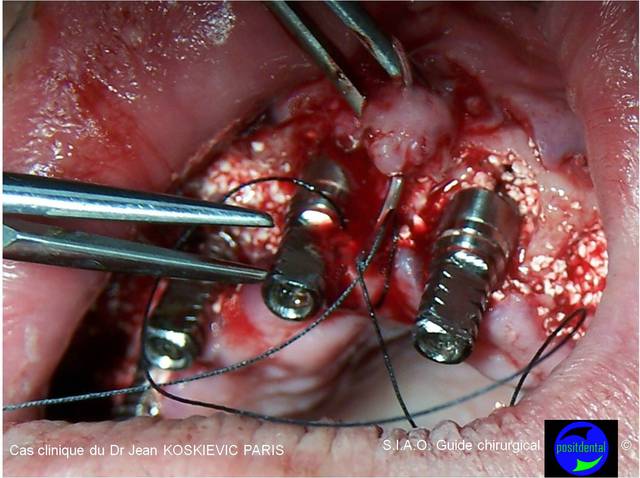

L'intervention se déroulant en 1 temps chirurgical et n'étant qu'un amateur, j'ai choisi des réglages simples en macro automatique afin de suivre le déroulé sans prise de tête.

Celle- là, j'aime bien car on ressent le geste du chirurgien.

Guide chirurgical dentaire 06 kl2oj5 - Eugenol